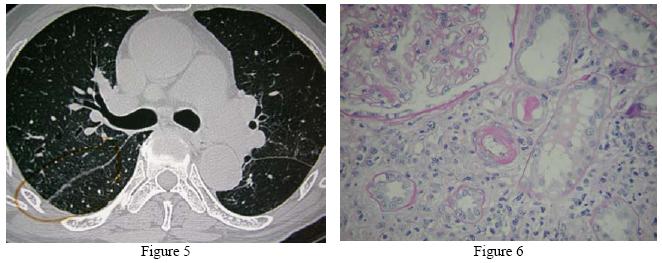

The submandibular glands enlargement persisted and he later developed episcleritis over the left eye. HRCT thorax on 18/10/2005 showed smooth septal thickening in both upper lobes, multiple tiny nodules with upper lobe predominance. Many were subpleurally located and ran along the fissures. The enlarged nodes still persisted over bilateral hilar & paratracheal region (Figure 5). Lung function test had been attempted for 16 times but all failed. A second FOB was repeated on 19/10/2005. It showed no endobronchial lesion. Biopsy from posterior segment of RUL & apical segment of RLL revealed fragments of lung tissue only, with focal fibrosis and scanty histiocytes. The cultures of bronchial aspirate were negative for bacteria, AFB & fungus. Renal biopsy was subsequently performed on 21/10/2005. It revealed the pathological diagnosis of non-granulomatous interstitial nephritis (Figure 6). Anti-nuclear factor screening was positive and the titre was 1:160. Other relevant investigations included HBsAg, Anti-HCV antibody, cryoglobulin, HIV, VDRL, ANCA , dsDNA and ENA , serum protein electrophoresis and urine BJP were all negative. A working diagnosis of sarcoidosis was thus fully established in view of the clinical, radiological and histological findings. Further investigations including Mantoux test (MT) 2, urine culture, urine for AFB culture, serum cryptococcal Ag, galactomannon, brucella antibody, toxoplasma antibody were negative subsequently. The serum lysozyme was elevated to 1771 u/ml (normal range: 150-500u/ml) but the serum angiotensin converting enzyme level was normal.